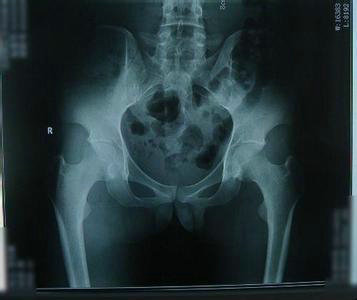

辅助检查:血常规示白细胞(WBC)9.0X109/L,血红蛋白(Hb)90g/L,血小板(PLT)531X109/L;24h尿蛋白定量0.96g;C-反应蛋白36.14mg/L;骶髂关节X线示:关节间隙变窄,可见虫蚀状破坏,部分硬化,双髋关节X线示:双髋臼缘、股骨头见多发囊变影,边缘硬化。

(图:患者双髋关节X光片图)